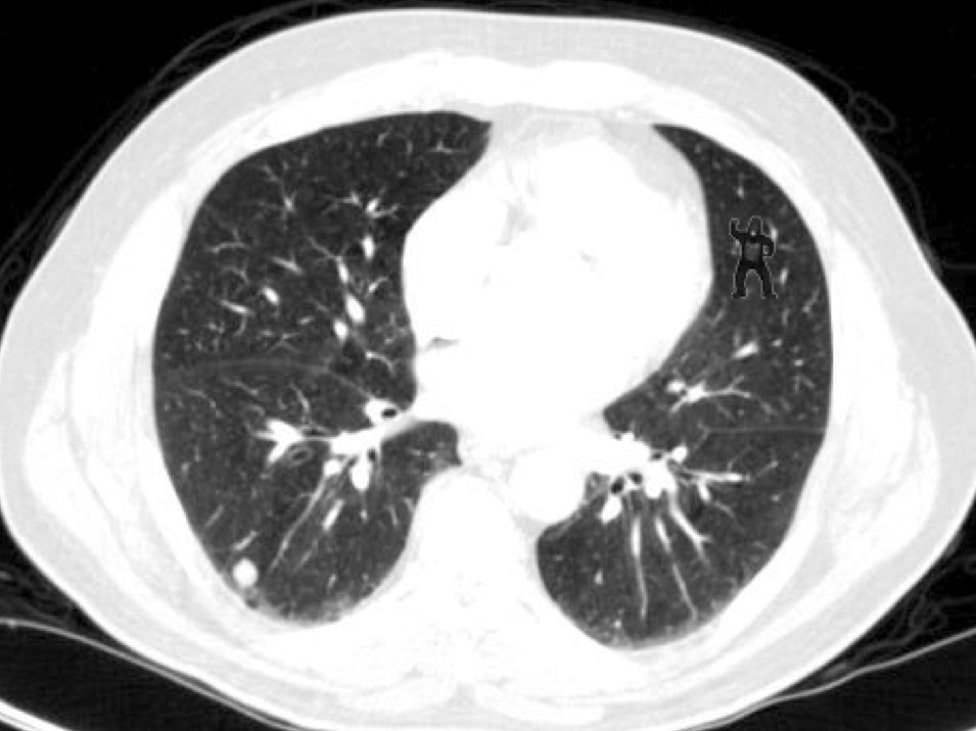

Here’s the image they were shown:

Did you see it? It’s not obvious to everyone, but the study dealt with professionals who are experts at scoping out even the smallest of irregularities. The gorilla, tacked on in the upper right side of the picture, is certainly something out of the ordinary.

Harvard researchers have found that 83% of radiologists—the people who review x-rays, CT scans, and MRIs—failed to find a gorilla hidden inside an X-ray image of a lung. The researchers put a tiny image of a gorilla on top of a lung scan and then asked radiologists to review the scan as they would any other, and look for anything out of the ordinary. The results showed that 83% of them couldn’t find the gorilla.